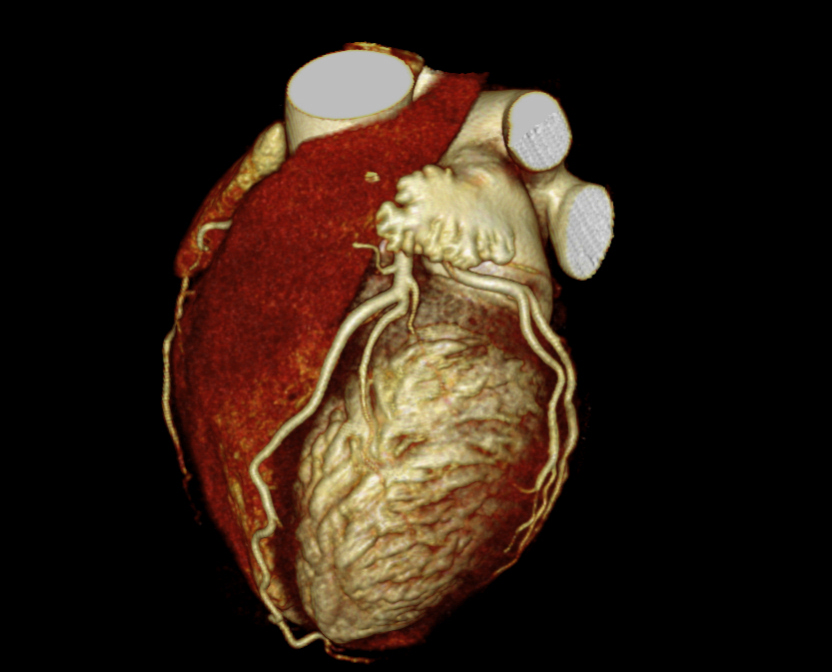

Fig. 3., 4., 5.: CT coronarography: Normal anatomy, volume rendered image and curved reformatted image Plaque causing stenosis on LAD coronary artery